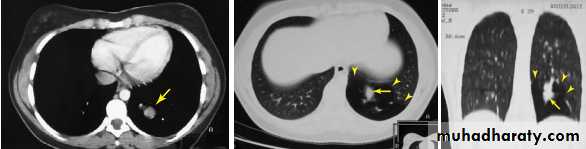

CT scan (Computed tomography scan )

Computed tomography or CT is an imaging modality that produces cross-sectional images representing the X-ray attenuation properties of

the body.